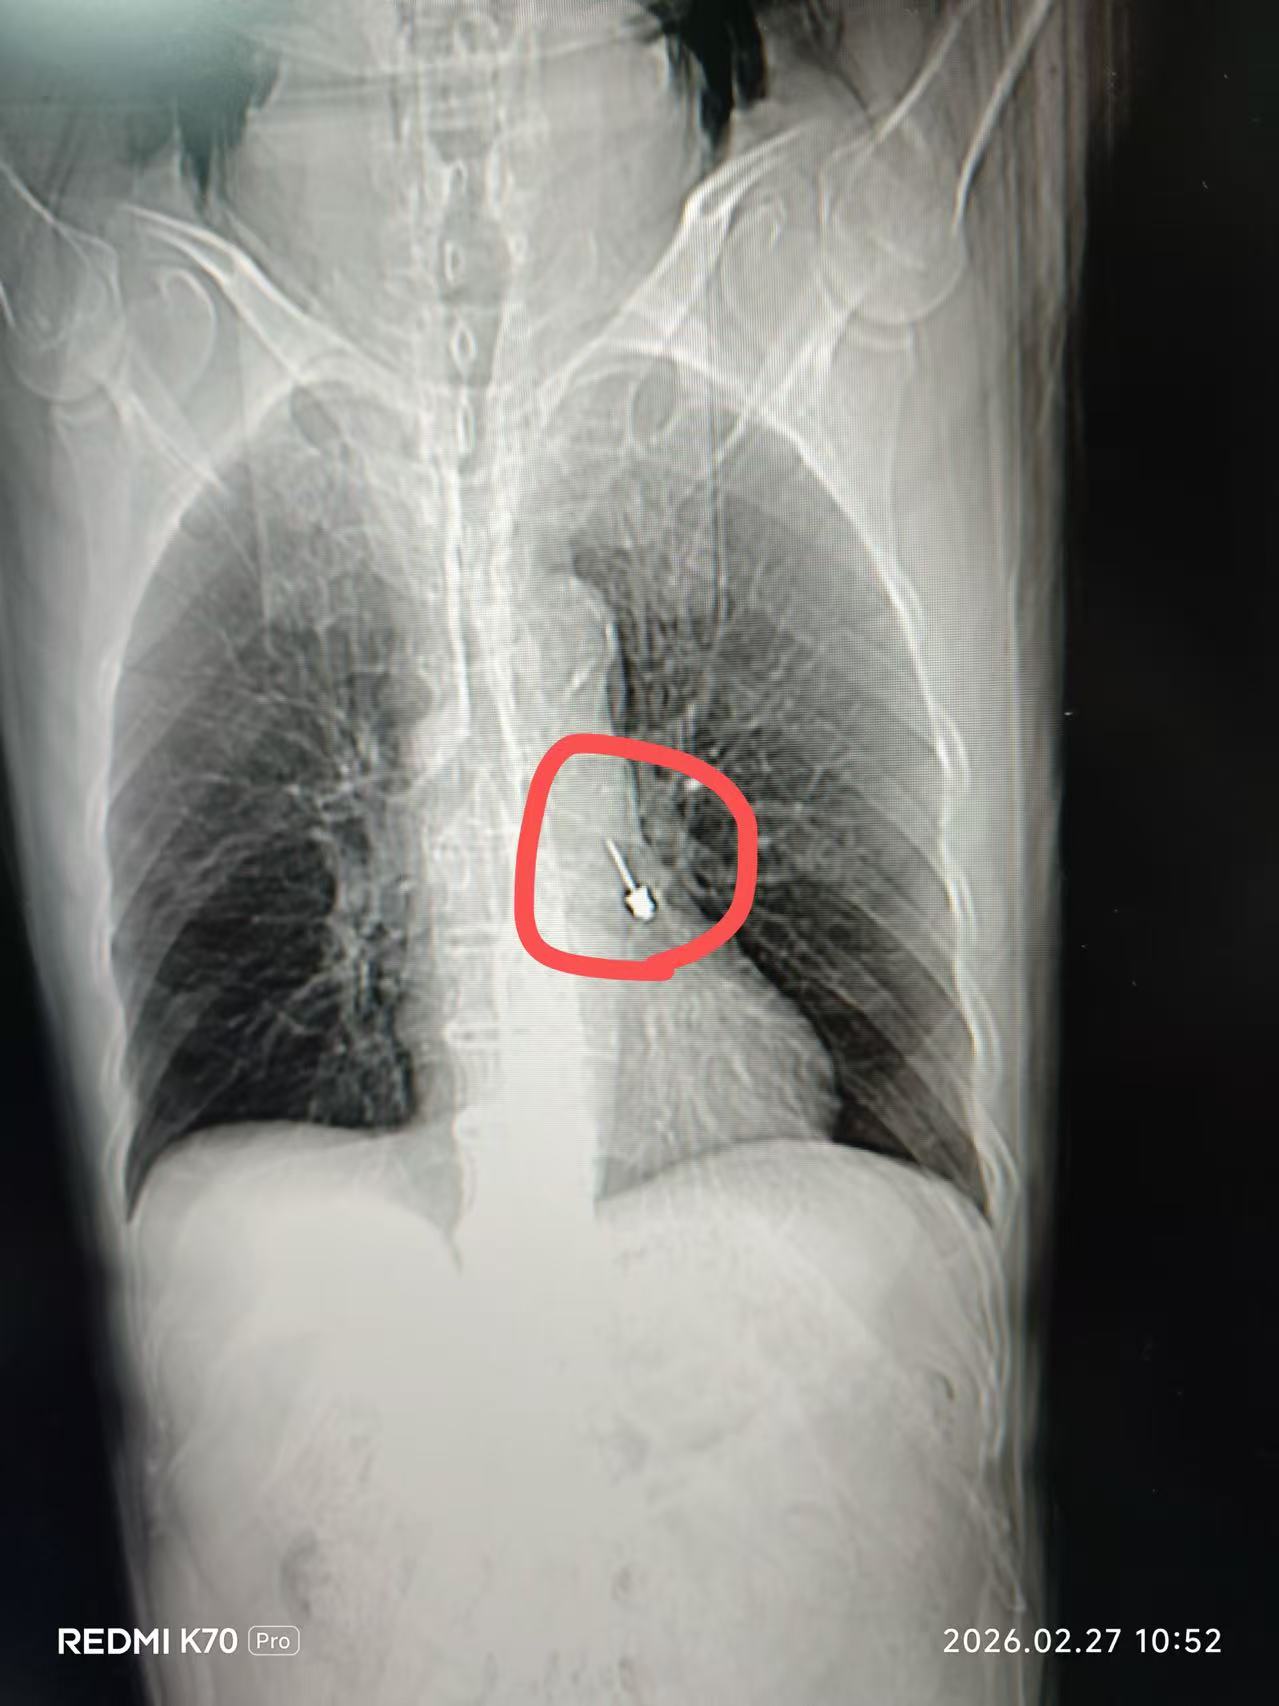

影像图

接诊医师查看李大爷的CT片后立即召集呼吸与危重症医学科会诊,会诊医师姜贺果副主任医师发现异物卡在左肺下叶近端支气管腔内,已经造成了中度气道梗阻,必须立即安排急诊手术。在科主任钱粉红的协调下,科室立即启动应急流程开展急诊手术。